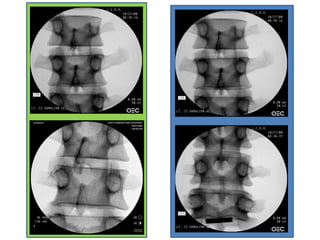

Fluoroscopy of the Lumbar Pedicle

• The lumbar pedicle is

oval shaped

• It should be projected

at the upper third of

the lumbar vertebra

• The AP tube is angled

to find the oval

appearance of the

Needle Placement

As the needle is advanced into the pedicle,

the position of the needle tip is checked

frequently in both planes.

On the AP view On the lateral view

The needle tip should not touch the

medial curve of the pedicle which

forms the wall of spinal canal.

The needle should be parallel to

the superior and inferior edge of

the pedicle.

Fluoroscopy of the

lumbar Pedicle

When the needle

reaches the junction of

the vertebral body in

the lateral view,

it should be still a space

between the tip of the

needle and the medial

pedicle in the AP view.